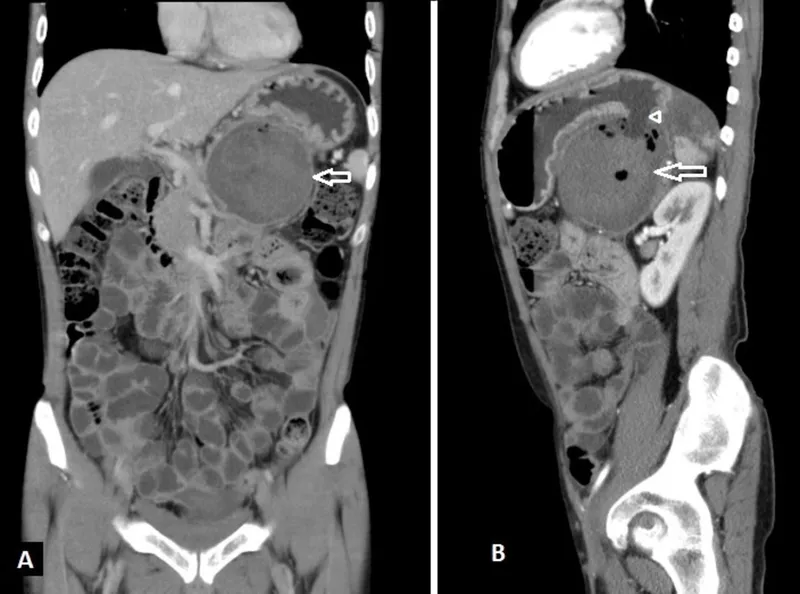

- CECT Abdomen: Confirms (wall forms ~4-6 wks), details size, location, complications (infection, hemorrhage).

⭐ CECT abdomen is the gold standard for diagnosing pancreatic pseudocysts (mature wall visible after 4-6 weeks) and assessing complications.

- Typically peripancreatic, frequently located in the lesser sac.